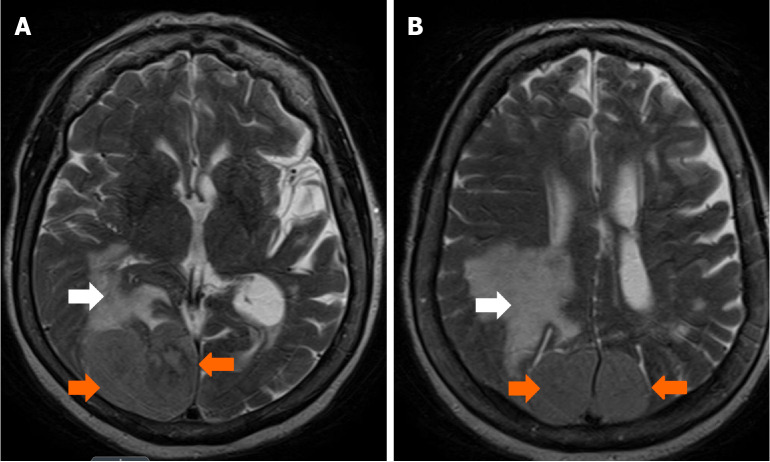

Case summary: We present a case describing a 78-year-old female who came in following a ground level fall. The primary assessment was notable for a history of similar recurrent falls and subtle left-sided peripheral visual field loss. Further neurological examination was otherwise largely unremarkable. A computed tomography scan of the head revealed a large extra-axial mass located along the posterior aspect of the falx. Follow-up magnetic resonance imaging confirmed a lesion measuring around 6.6 cm × 4.2 cm × 5.5 cm. A partial surgical resection of the right-sided portion of the lesion was performed. Complete resection was limited by insufficient visualization and challenges with hemostatic control of the left parafalcine region. Further histopathological analysis confirmed a fibrous meningioma with focal necrosis, consistent with World Health Organization Grade 2 classification. She was subsequently scheduled for outpatient follow-up to assess the residual tumor management.